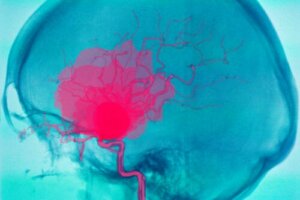

An intracerebral hemorrhage is a serious situation that can put a person’s life at risk. It consists of bleeding inside the brain. Because of this, other body parts are deprived of oxygen.

An intracerebral hemorrhage, as we mentioned in the introduction, is bleeding that occurs inside the brain. It usually causes sudden-onset neurological defects and even coma.

This is due to the lack of blood supply to other parts of the brain, since the blood doesn’t continue its journey through the blood vessels. It’s important to distinguish between intracerebral and intracranial hemorrhage.